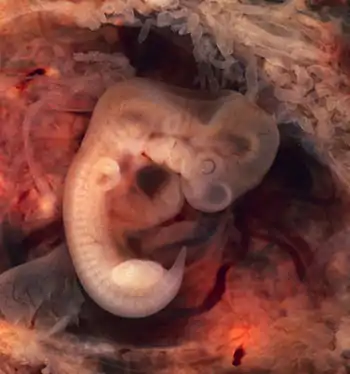

Selected image –

Photo credit: Public domain (U.S. Brookhaven National Laboratory)